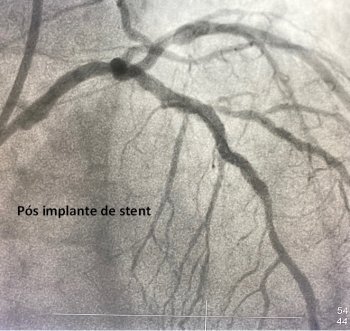

Nos dias atuais, na grande maioria dos casos é possível tratar estas obstruções de maneira menos invasiva por meio da angioplastia com implante dos stents coronários. A angioplastia consiste na dilatação das obstruções utilizando um cateter balão e, posteriormente, o implante das próteses metálicas, chamadas de stents. Geralmente, a angioplastia coronária é realizada no mesmo procedimento da cinecoronariografia apenas naqueles pacientes internados devido a quadros coronarianos agudos (como a angina instável e o infarto do miocárdio). Já nos pacientes estáveis, o cateterismo diagnóstico é realizado de maneira ambulatorial e a angioplastia programada para um outro momento.